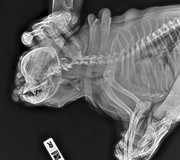

Коллапс трахеи форум

Коллапс трахеи форум 116 фотографий